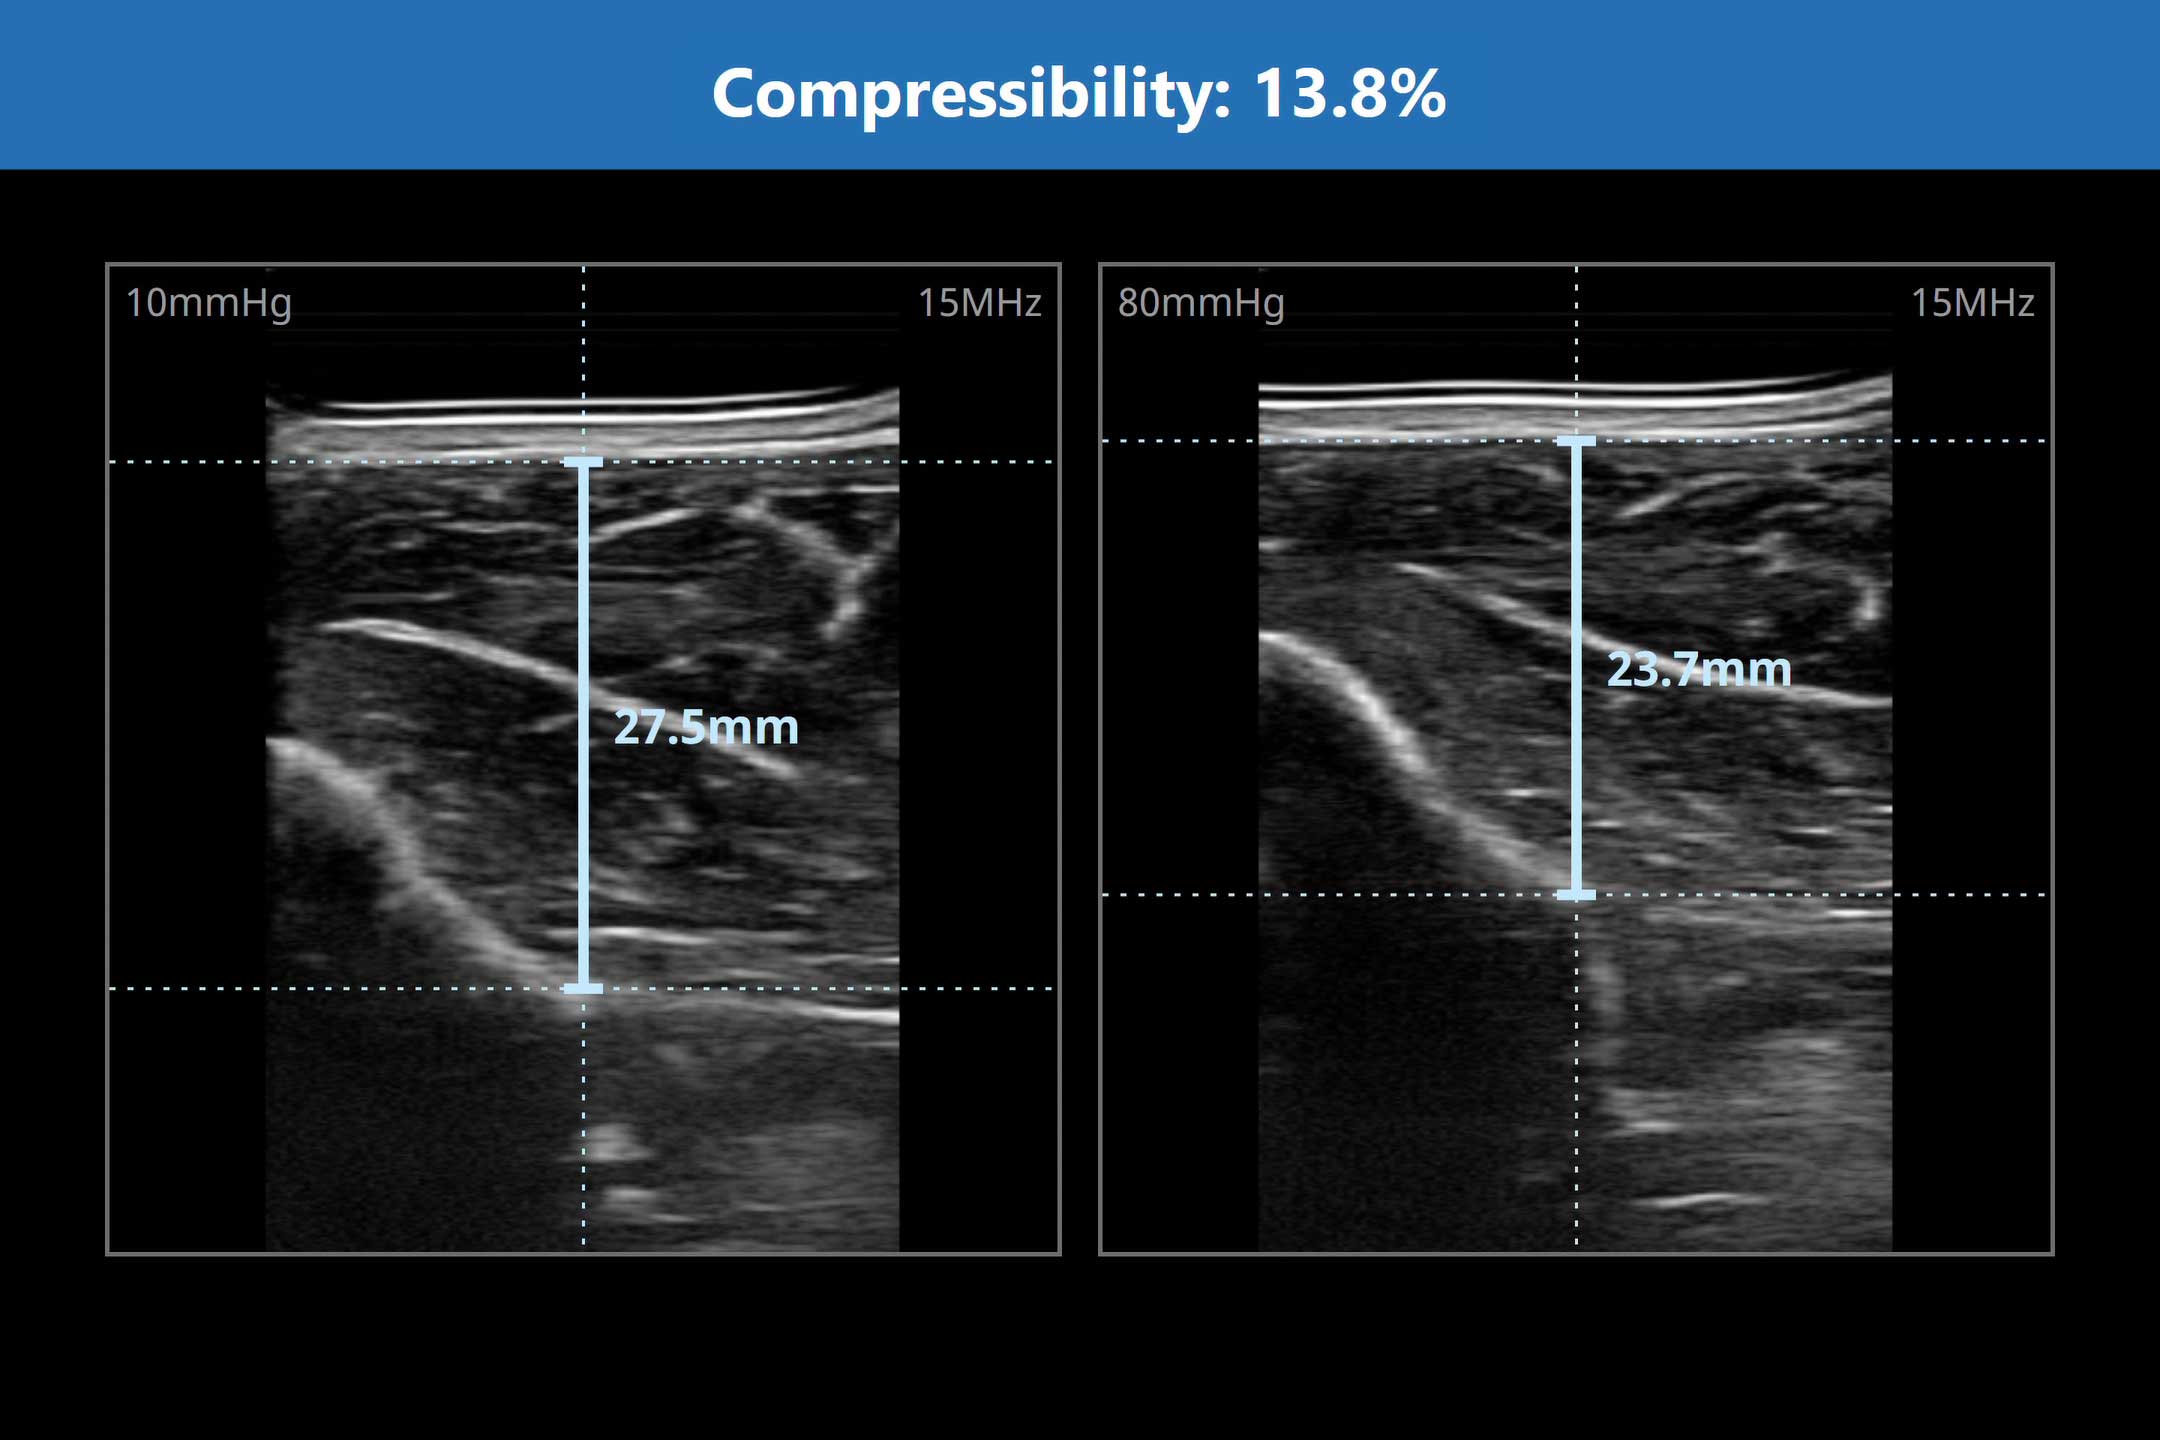

What is Compressibility?

Compressibility is a quantified metric that measures how soft tissue responds to pressure, reflecting swelling, tension, or resilience. It provides a dynamic view of tissue health, in real-time.